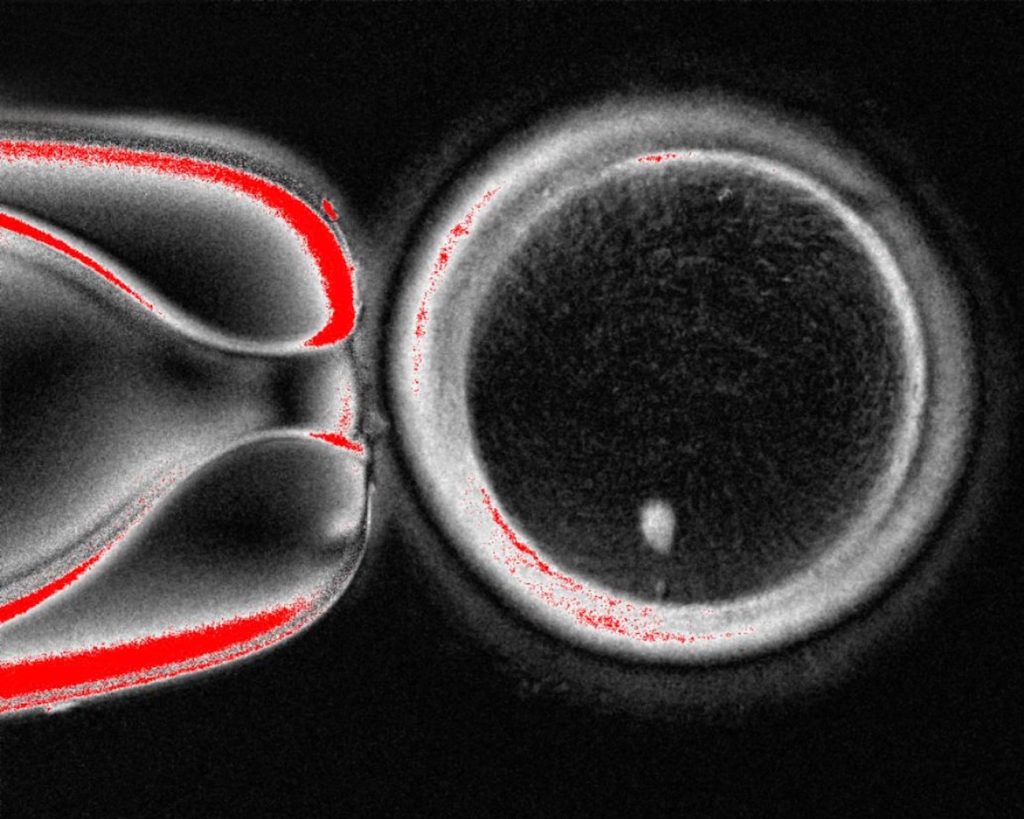

دانشمندان آمریکایی موفق شدند با استفاده از DNA سلولهای پوست انسان، تخمک بسازند و پس از بارورکردن آنها با اسپرم، جنینهای انسانی در مراحل اولیه را خلق کنند. این دستاورد امیدهای جدیدی را برای درمان ناباروری ایجاد میکند، البته با مسائل فنی و اخلاقی بزرگی هم روبهرو است.

براساس گزارش BBC، روش محققان دانشگاه بهداشت و علوم اورگان داستان ساده لقاح را بهکلی تغییر میدهد. فرایند جدید در چند مرحله پیچیده انجام میشود: ابتدا، محققان هسته یک سلول پوست را که حاوی مجموعه کامل ۴۶ کروموزوم فرد است، خارج میکنند. سپس، این هسته را به یک تخمک اهدایی که هسته خودش از آن خارج شده، منتقل میکنند؛ روشی که یادآور تکنیک استفادهشده برای شبیهسازی گوسفند معروف، «دالی»، است.

اما این تخمک هنوز آماده لقاح نیست، زیرا ۴۶ کروموزوم دارد، درحالیکه یک تخمک سالم باید ۲۳ کروموزوم داشته باشد. در مرحله بعدی، دانشمندان با استفاده از یک ترکیب شیمیایی تخمک را وادار میکنند تا نیمی از کروموزومهای خود را بهصورت تصادفی دور بریزد. پس از این مرحله، تخمک مصنوعی با ۲۳ کروموزوم آماده است تا با اسپرم بارور شود.